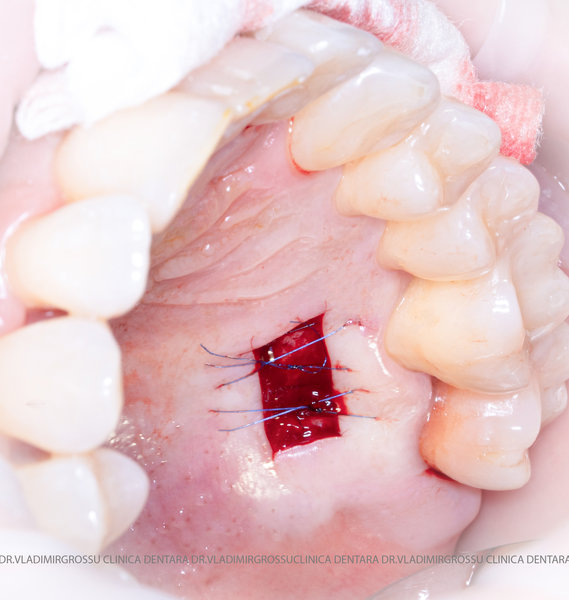

Un element esențial în procedura de aditie osoasă este utilizarea membranelor biologice, care izolează materialul osos de țesuturile moi (gingie) pe durata procesului de vindecare. Cele mai recomandate sunt membranele resorbabile din colagen sau pericard.

Adiția de gingie (gingivoplastia)

Aditia gingivală este o procedură chirurgicală ce corectează diverse probleme estetice și funcționale, cum ar fi recesiunea gingivală. În implantologia modernă, aditia de țesut moale este utilizată aproape în fiecare intervenție de inserție a implantului dentar pentru a asigura un aspect estetic natural și o bună integrare a implantului în cavitatea bucală.